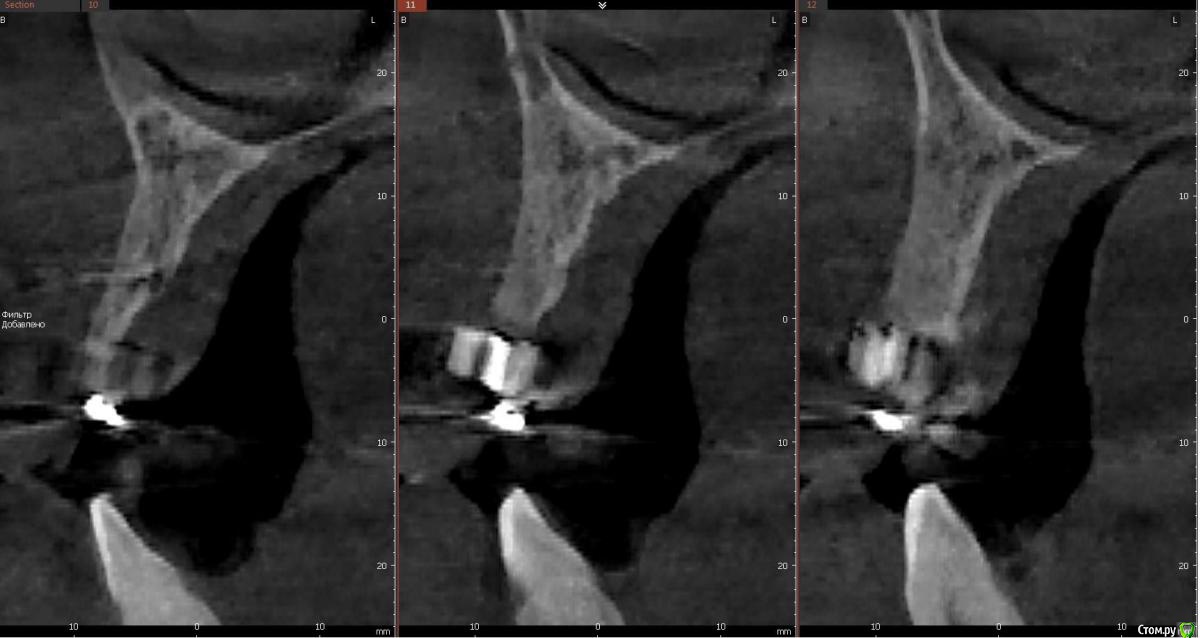

kamranchick Опубликовано 30 мая, 2018 Поделиться Опубликовано 30 мая, 2018 Реколы первые 1 Ссылка на комментарий

АнтонТЛТ Опубликовано 30 мая, 2018 Поделиться Опубликовано 30 мая, 2018 (изменено) Чет как-то не ахти. Как думаешь в чем причина? Пробки неподвижны? Изменено 30 мая, 2018 пользователем АнтонТЛТ Ссылка на комментарий

kamranchick Опубликовано 30 мая, 2018 Поделиться Опубликовано 30 мая, 2018 Чет как-то не ахти. Как думаешь в чем причина? Пробки неподвижны?Пробки намертво приклеены.Причина не знаю в чем(Это провал, ибо пациент готовится на имплантацию уже.Тут даже 3.5 с трудом проходит 1 Ссылка на комментарий